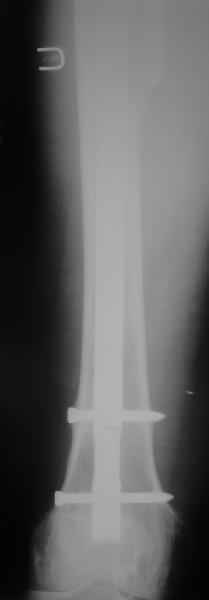

Пациента удалось осмотреть недавно. Достигнутый результат сохраняется. Перелом бедра сросся. Конечность опорная и безболезненная, ходит без трости. Ножка, похоже, реинтегрировалась, как и надеялись. Снимки и фото в приложении. Комментарии приветствуются.

Надо ли что-то делать дальше, как полагаете? Убрать винты? Убрать "удлинитель ножки"? Или оставить все, как есть? Спасибо заранее.